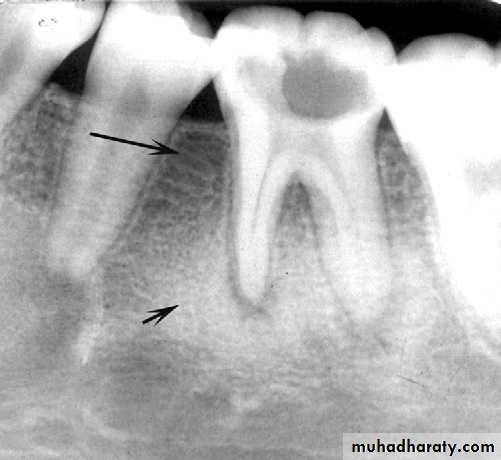

Widening of the periodontal membrane space

It is important to observe whether the widening is uniform or irregular and whether the lamina dura is still present. For instance, orthodontic movement of teeth results in widening of the periodontal membrane space, but the lamina dura remains intact. Malignant lesions can quickly grow down the ligament space, resulting in an irregular widening and destruction of the lamina duraSurrounding Bone Reaction